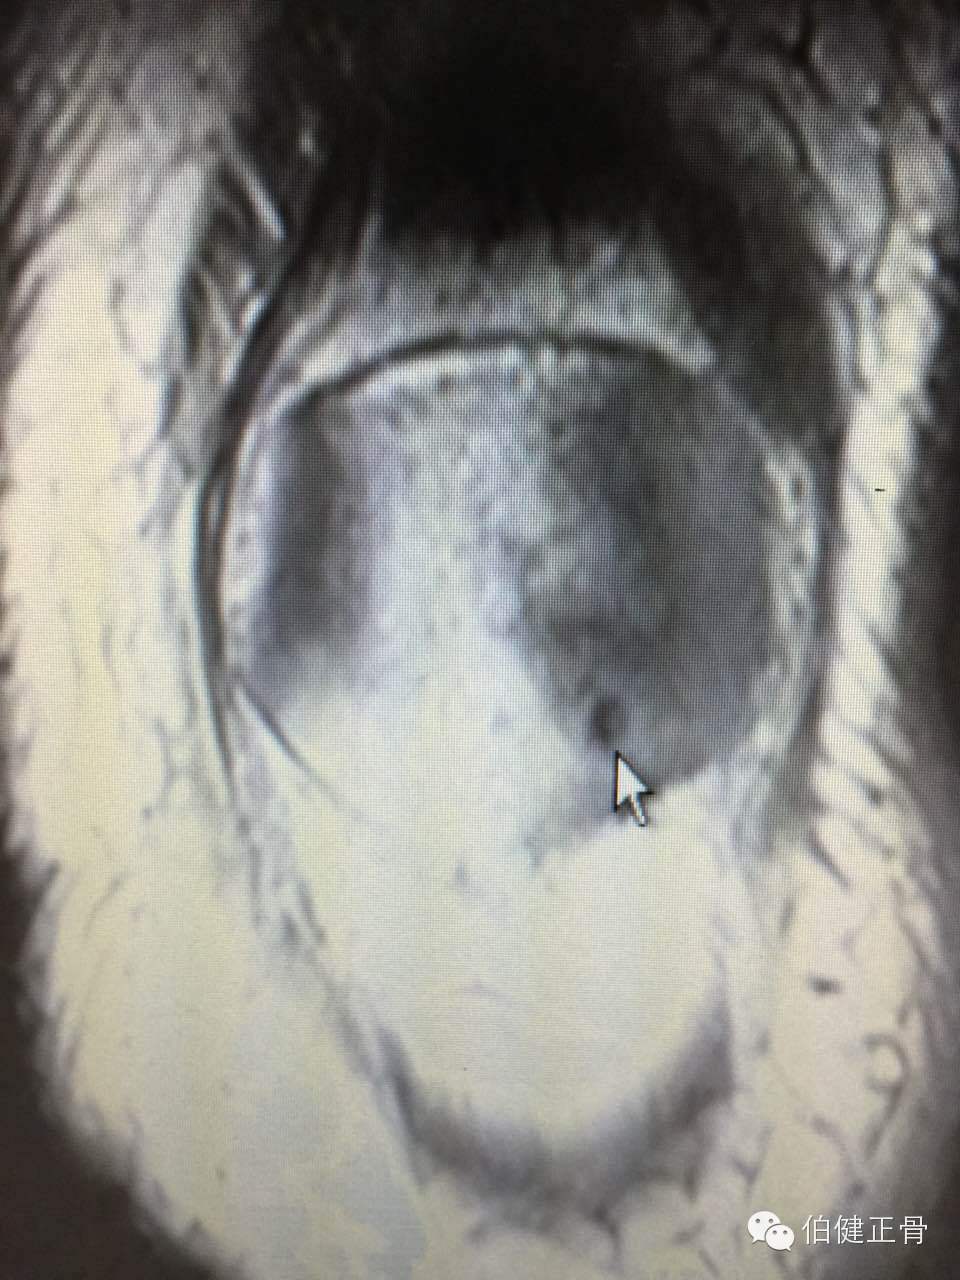

附髌骨软化症的诊断:

3.X线检查:照膝关节正,侧位及髌骨切线位X线片,早期无异常所见,晚期可因软骨大部磨损,髌骨与股骨髁部间隙变窄,髌骨和股骨髁部边缘可有骨质增生。

诊断髌骨软化症的主要依据是髌骨后的疼痛,髌骨压磨试验和单腿下蹲试验引起髌骨后疼痛,应该注意检查有无合并半月板损伤和骨关节炎等。